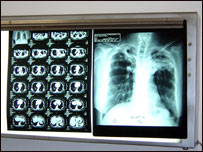

د نري رنځ کتنه

د افغانستان د روغتيا وزارت اعلان وکړ چې په هيواد کې د نري رنځ ناروغي پنځوس په سلو کې راټيټه شوې ده .